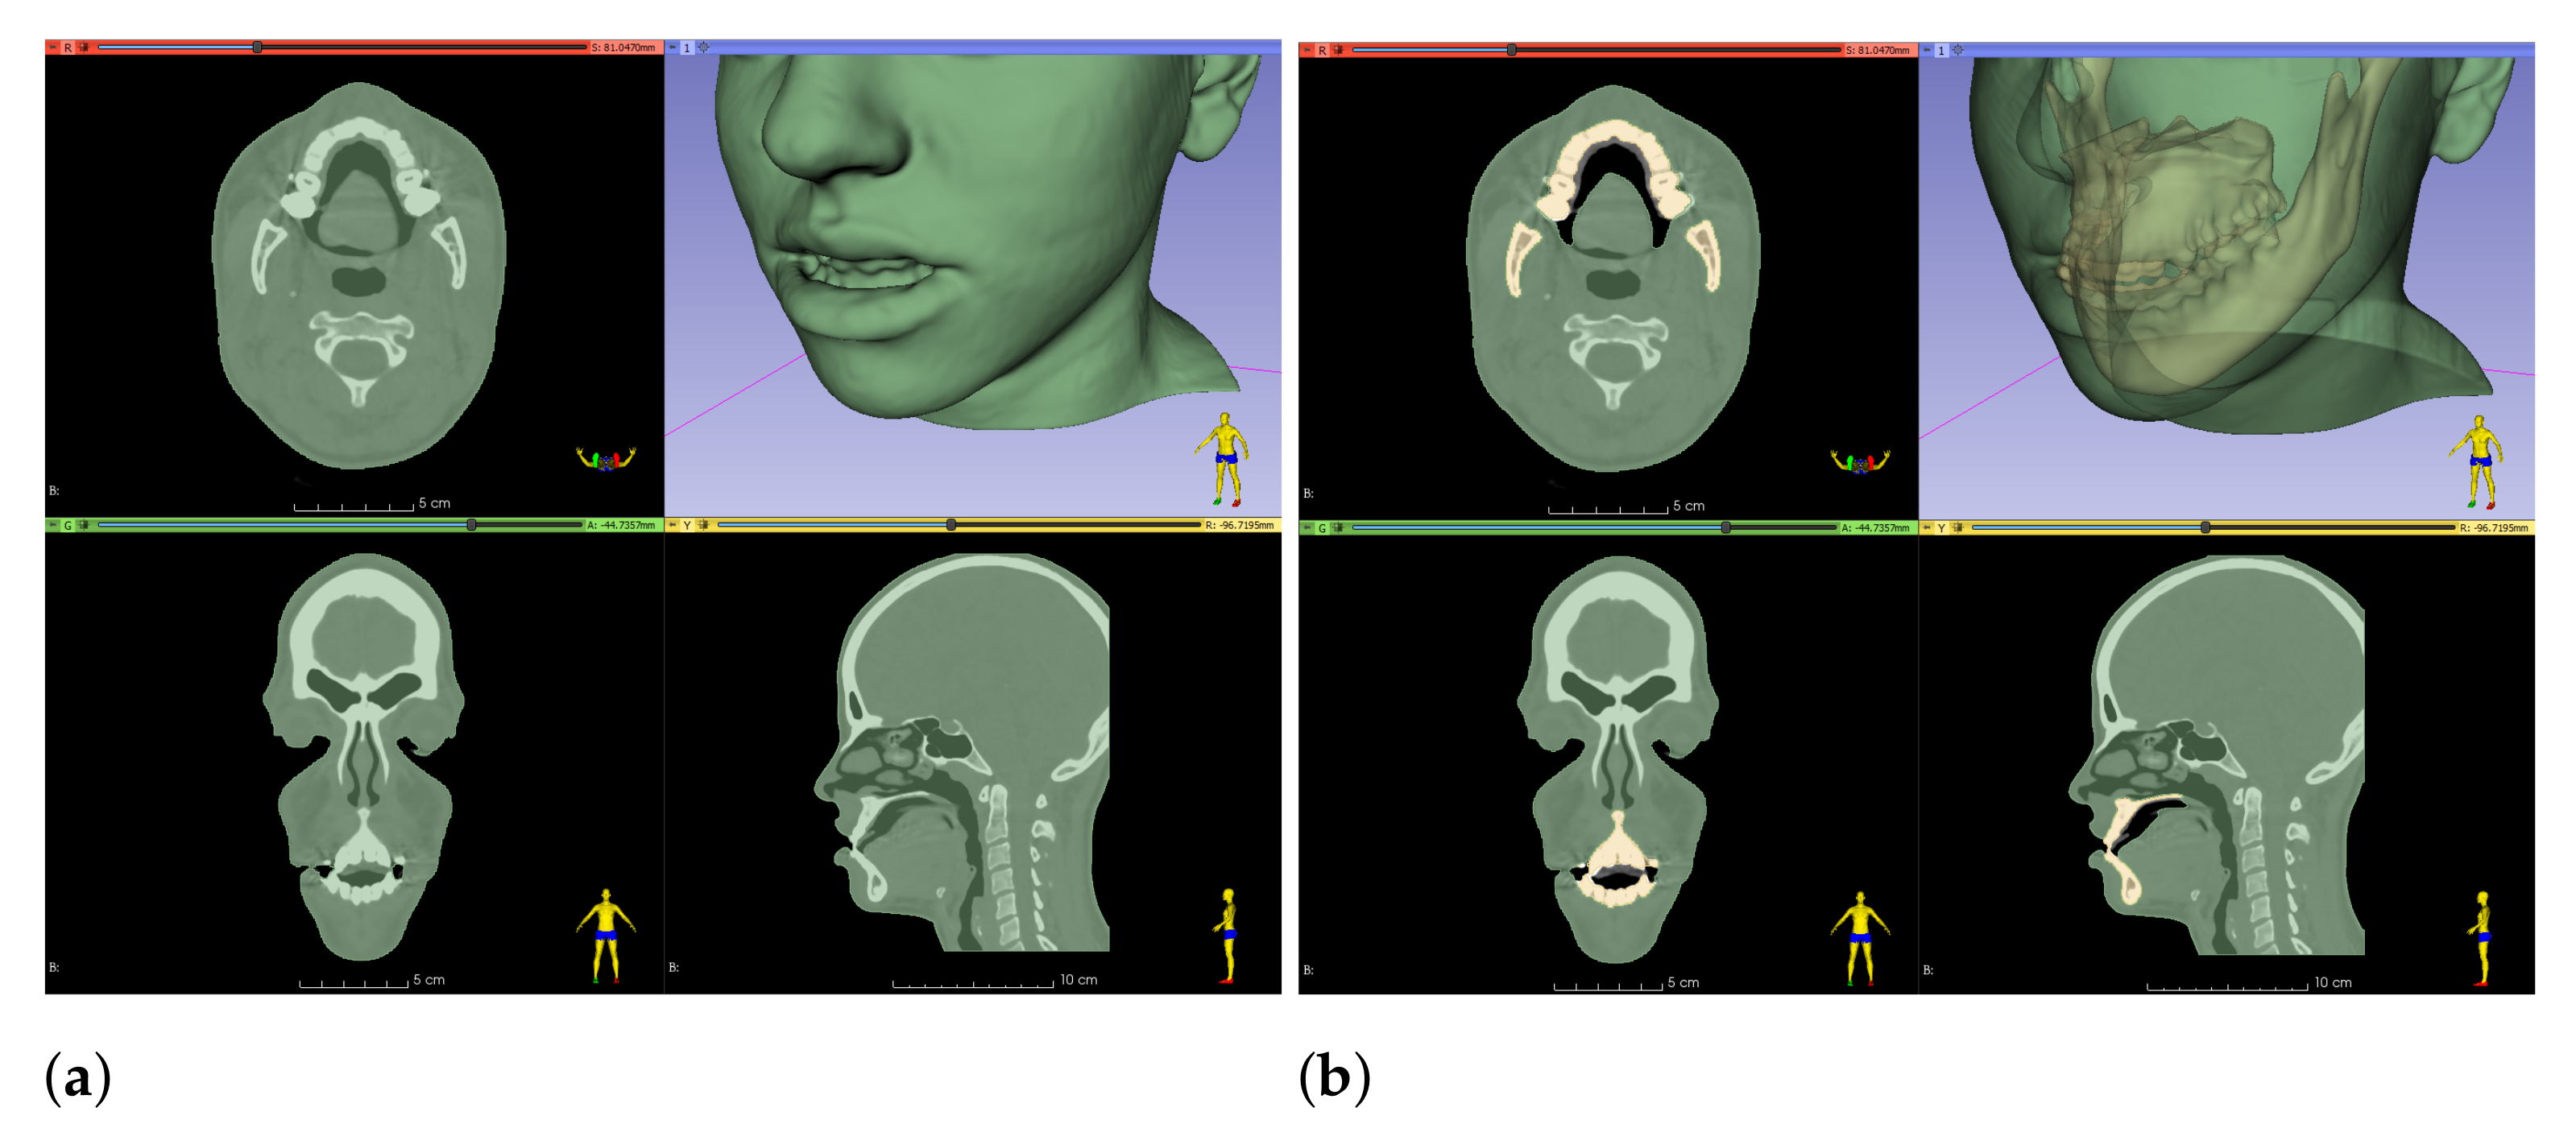

2.5. Preparation of Simulation Meshes and Couplings

2.5.1. Bones

2.5.2. Soft Tissue